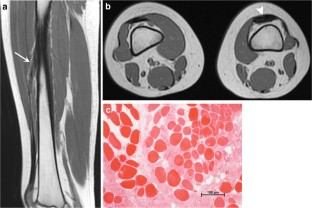

All patients presented with progressive unilateral restricted knee flexion and had multiple imaging studies targeting the knee before diagnosis. Diagnosis in all patients was made on MRI of the thighs, which demonstrated a fusiform low signal intensity structure with muscle-like architecture arising from the anterior or anterolateral proximal femur and blending with the common quadriceps tendon distally. All patients underwent surgical release of the anomalous band with significant functional improvement.

Fig. 3